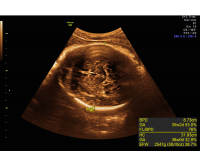

How is this condition managed during pregnancy?

When identified during pregnancy, a detailed evaluation of the brain by fetal MRI is recommended. As other physical malformations and genetic abnormalities may be associated with this finding, genetic counseling and testing are recommended. Prenatal consultations with pediatric neurology specialists may be recommended to discuss the condition and its prognosis.

ACC MRI sagittal view